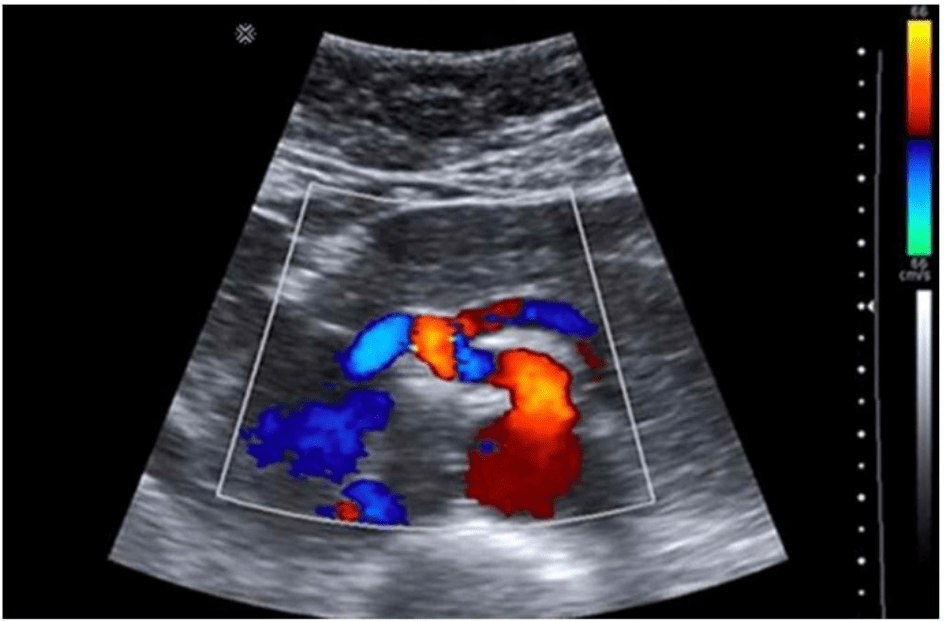

The absence of which sonographic finding indicates the acute process depicted in these images?